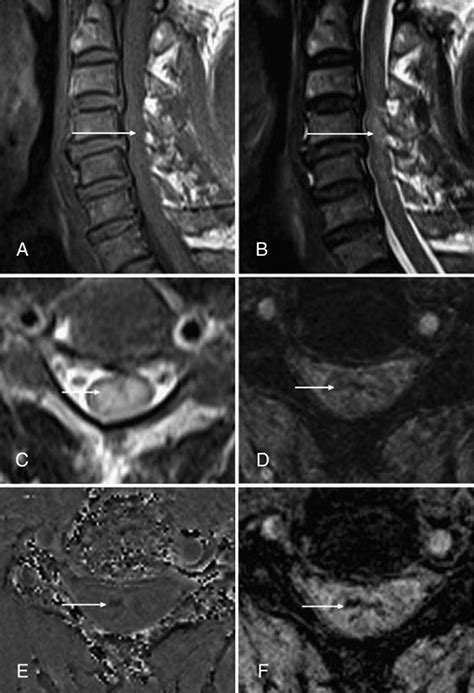

The versatility of Susceptibility Weighted Imaging allows it to play a pivotal role in several clinical domains. Its ability to detect microbleeds, which are often invisible on traditional T1-weighted or T2-weighted scans, is perhaps its most celebrated application. The following list highlights key clinical scenarios where this imaging modality is considered the gold standard:

• Traumatic Brain Injury (TBI): SWI is highly sensitive to the detection of Diffuse Axonal Injury (DAI) and microhemorrhages resulting from shear forces during trauma.

Implementing Susceptibility Weighted Imaging requires specific hardware and software considerations. High-field MRI scanners, typically 3 Tesla or higher, are preferred because the susceptibility effect is more pronounced at higher field strengths. The acquisition involves 3D gradient-echo sequences with long echo times to maximize the phase shifts caused by the magnetic susceptibility differences.

Radiologists look for "blooming effects" on the images, where small, dark spots represent paramagnetic substances like blood products. Because the signal decay is accelerated in regions with high iron or deoxyhemoglobin content, these areas appear as dark, high-contrast signals. Interpreting these images requires an understanding of how to differentiate between normal venous blood and pathological hemorrhages. For instance, the presence of blood in deep brain nuclei versus the cortex can indicate vastly different underlying etiologies, such as hypertensive vasculopathy or cerebral amyloid angiopathy.